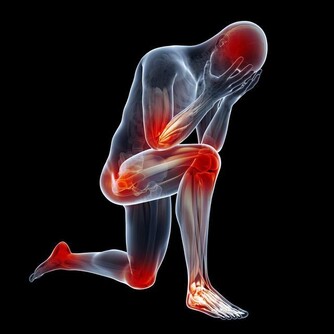

膝蓋關節一直是諸多長輩的困擾 尤其到了中老年又缺乏運動的情況下 很容易伴隨著天氣或者其他原因而不適 可是沒想到這些問題讓一顆便宜隨處可見的洋蔥改善了! 做法: 材料:洋蔥2個,紅葡萄酒500毫升,1瓶普通紅葡萄酒配三個洋蔥。 製法:將洋蔥洗凈,去掉表麵茶色外皮,切成八等份約半月形 將洋蔥洗凈,去掉表將洋蔥裝入玻璃瓶內,加入紅葡萄酒,(將剝下來的外皮也一起加入效果更好 將玻璃瓶蓋好密封,在陰涼地方放置約2至8日。(筆者覺得一星期最好) 將玻璃瓶的洋蔥片,用濾網過濾後,洋蔥、酒分開裝入瓶中,放置在冰箱中冷藏 飲用方法: 一. 每日約一杯(50毫升),年紀大的人每次20毫升左右; 二. 每日飲一至兩次; 三. 浸過酒的洋蔥片一起食用更好; 四. 不喝酒的人,可用兩倍左右的開水稀釋後飲用或每次倒入電鍋內煮約4至5分鐘,蒸發酒精後飲用。 洋蔥治療膝蓋疼效果驚人 看到這裡大家是否覺得很容易呢?究竟又可以治那些病呢? 讓筆者告訴大家,其功效對膝蓋! 疼痛、白內障、老人痴呆的效果相當驚人,日本非常流行。 一. 高血壓的患者,飲了之後血壓正常且安定,也會降低糖尿值,把血糖下降。 二. 每晚都要去幾次廁所的夜晚頻尿症,喝了兩天之後,不可思議的完全恢復正常。 三. 每天夜裡醒來,一直到天亮都不能再入睡的,不食安眠藥不能入睡的不眠症,飲用之後也會全消除。 四. 經常肚子會脹,非常痛苦的便秘症,喝了之後第二天便恢復正常排便。 吃洋蔥的好處 補充:討厭吃洋蔥嗎?看看下面的文章,即使它再不可口,為了身體好,也請多多食用。 【洋蔥比骨質酥鬆症的藥有效】 權威期刊「自然」的最新研究報告指出,洋蔥是最能夠防止骨質流失的一種蔬菜。洋蔥預防骨質流失的效果,甚至比骨質酥鬆症治療藥品還要好。 【洋蔥可以預防膽固醇過高】 據哈佛醫學院心臟科教授克多格爾威治博士指出,每天生吃半個洋蔥,或喝等量的洋蔥汁,平均可增加心臟病人約30%的HDL含量(HDL為高密度脂蛋白膽固醇,一種被認為有助於預防動脈粥狀硬化的膽固醇,也是一種的好的膽固醇。) 【洋蔥可以分解脂肪】 克多博士讓診所里的心臟病人每天吃洋蔥,結果發現洋蔥里所含的化合物也能阻止血小板凝結,並加速血液凝塊溶解。所以,當你享用高脂肪食物時,最好能搭配些許洋蔥,將有助於抵銷高脂肪食物引起的血液凝塊;所以說牛排通常搭配洋蔥一起吃,是很有道理的。 【洋蔥可以對抗哮喘】 洋蔥含有至少三種抗發炎的天然化學物質,可以治療哮喘。由於洋蔥可以抑制組織胺的活動,而組織胺正是一種會引起哮喘過敏症狀的化學物質;據德國的研究,洋蔥可以使哮喘的發作機率降。 【洋蔥可以治療糖尿病】 很久以前,洋蔥就被用來治療糖尿病,到了現代,醫學也證明洋蔥確實能夠降血糖;而且不論生食或熟食,都同樣有效果。原來洋蔥里有一種抗糖尿病的化合物,類似常用的口服降血糖劑甲磺丁胺,具有刺激胰島素合成及釋放的作用。